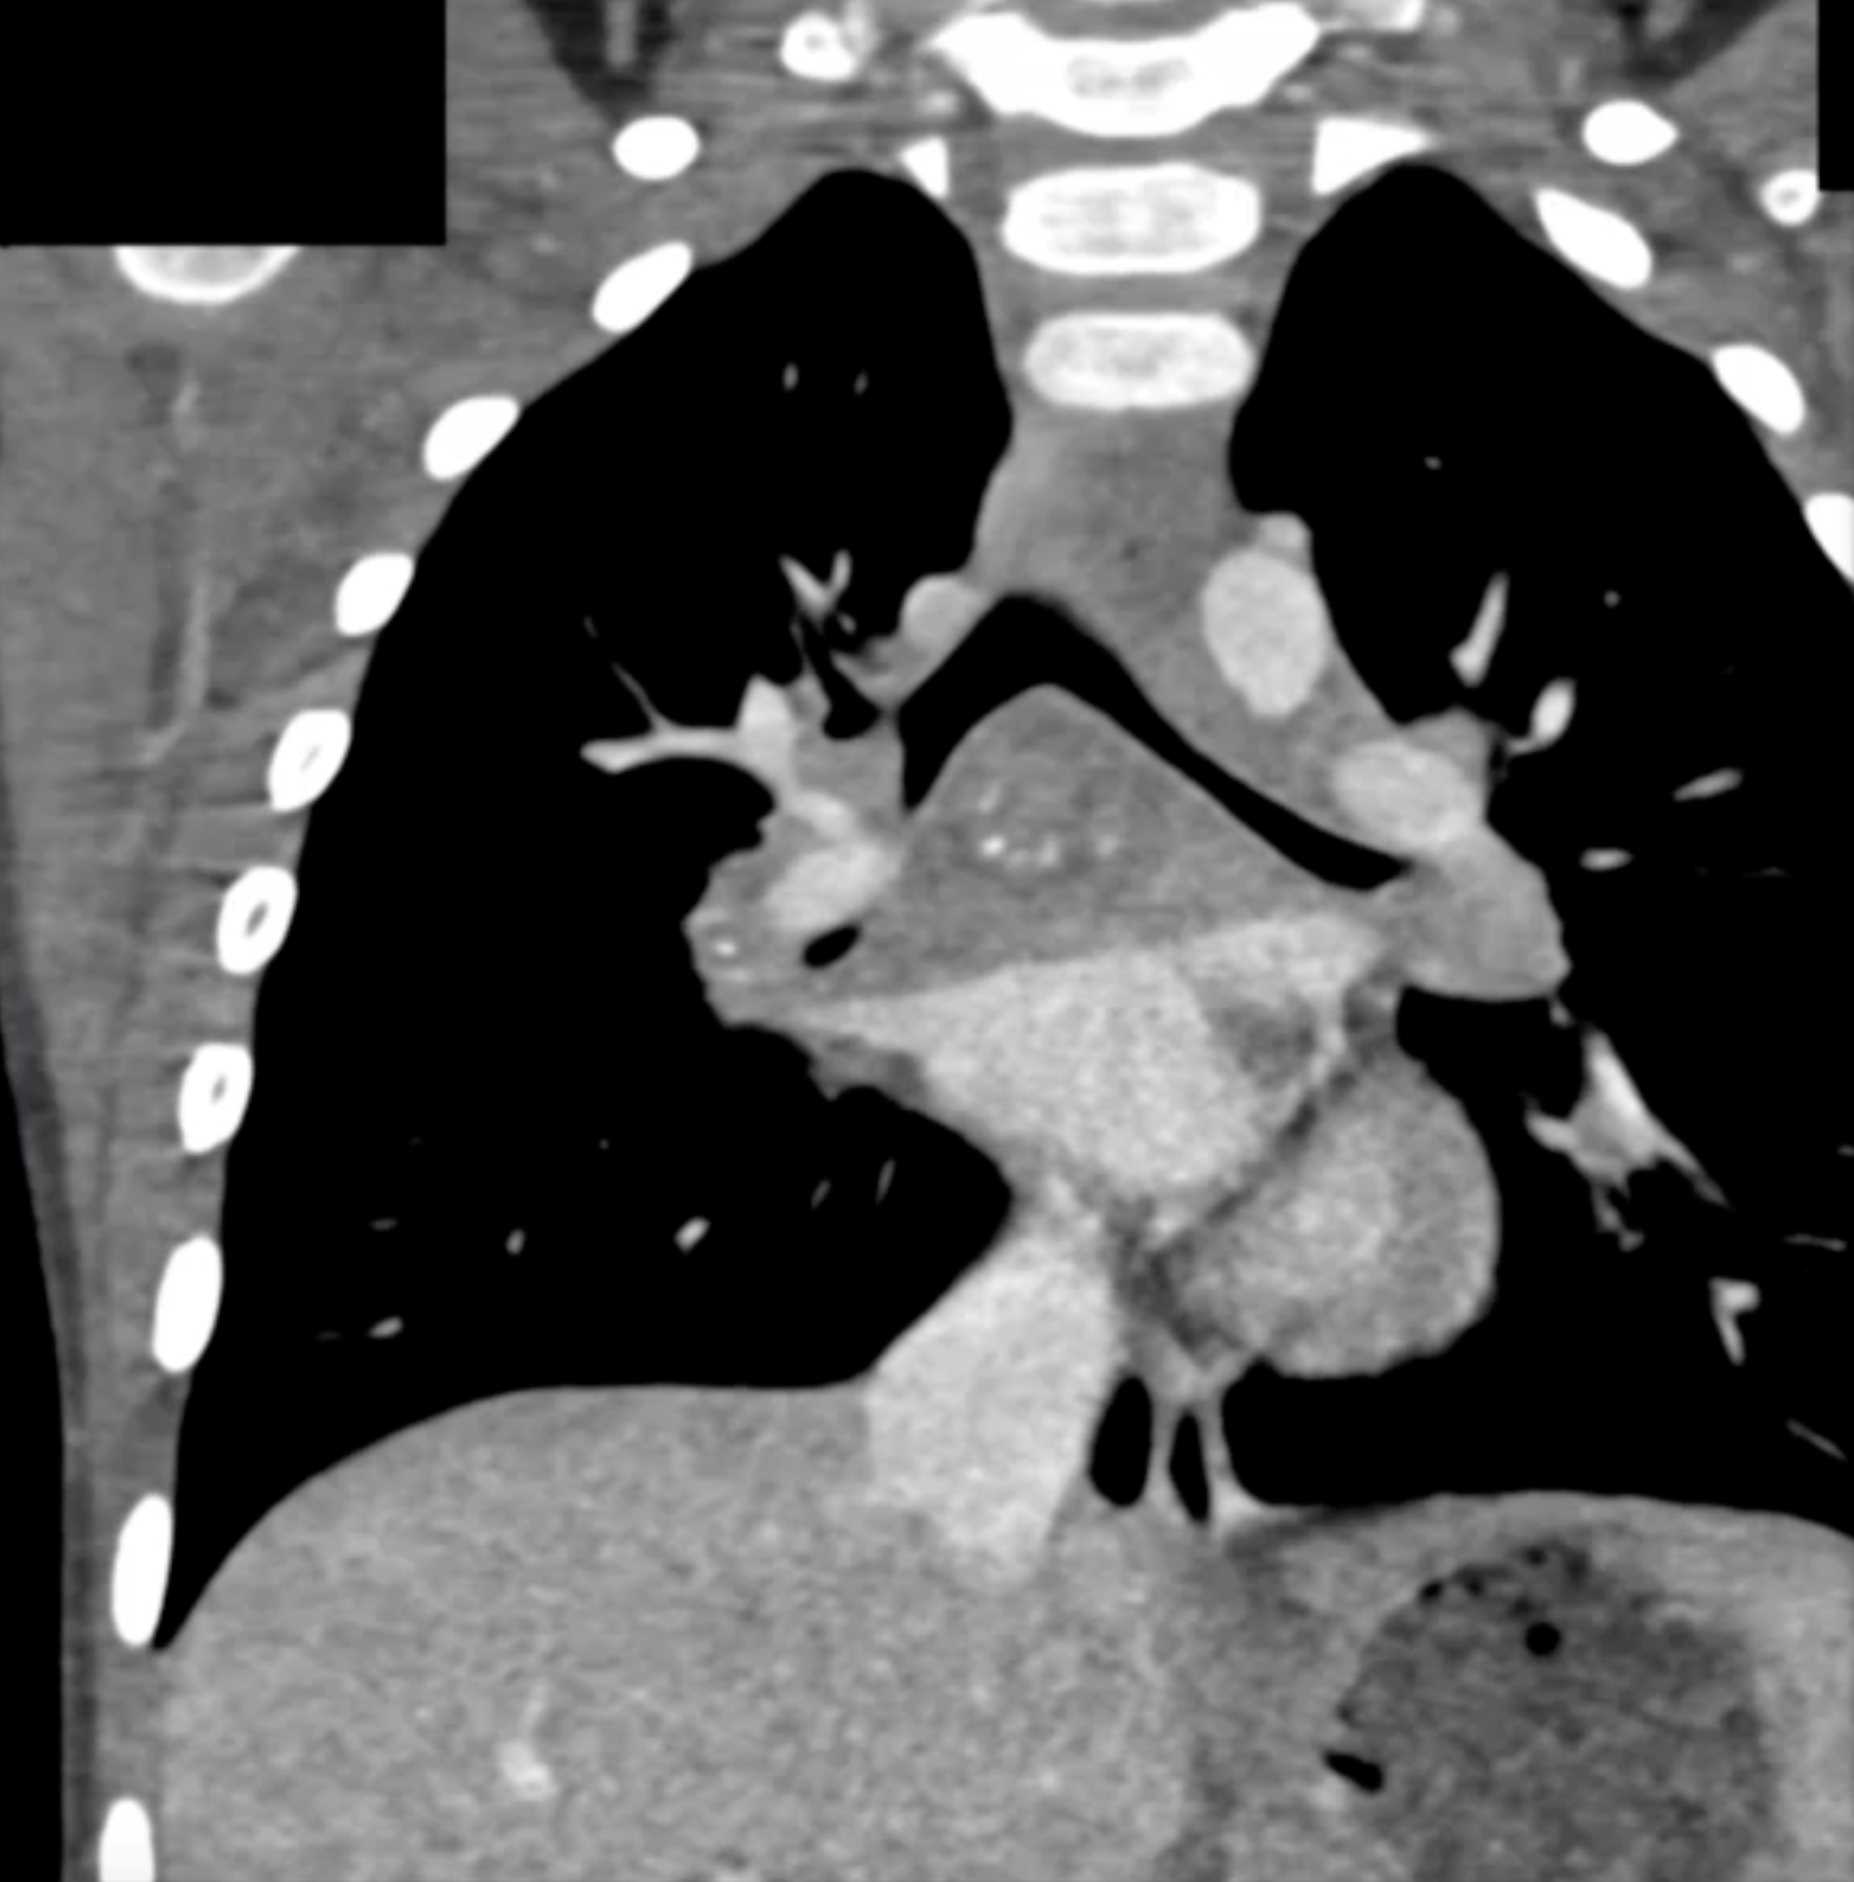

Histoplasmosis and Normal Thymus